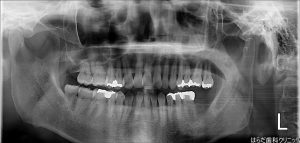

最後にレントゲンを撮影し、しっかりとインプラント体

が埋入されている事を確認しています。

下の画像で見ると左右反転するので右下の所に埋入されて

いるのがわかります‼

また、下の画像は左下7番のインプラント埋入前

の画像です。こちらも左右反転しているので

右下一番奥の歯がない部分に埋入しました。